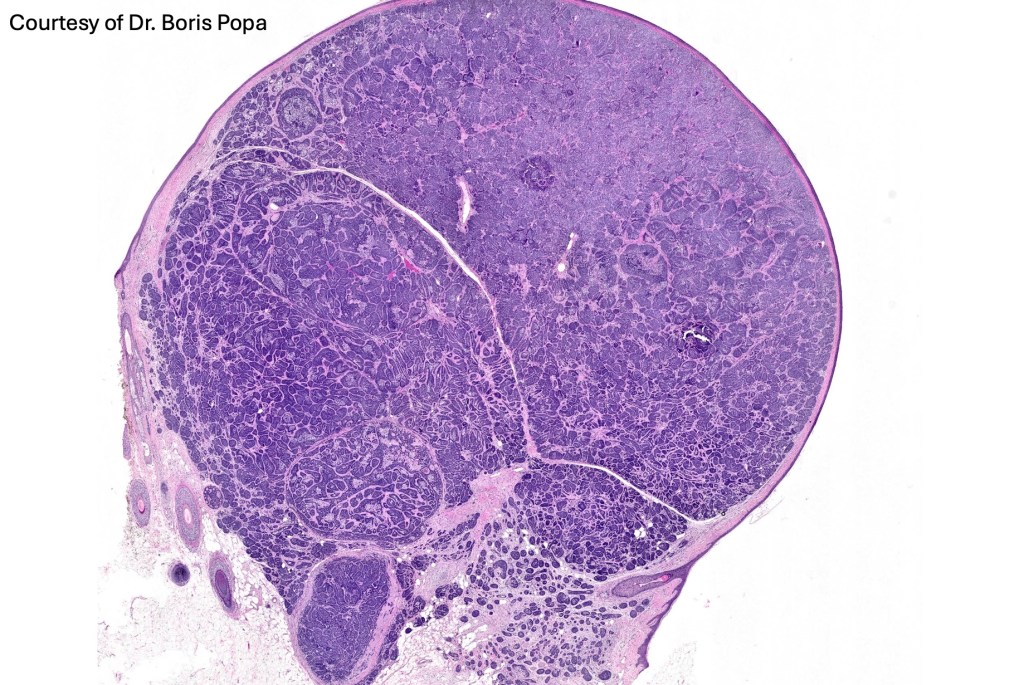

Histological features

•Dermal based

•Jigsaw/mosaic pattern arrangement of variably sized lobules of tumor cells with surrounding think, eosinophilic hyaline basement membrane

•Intralobular hyaline basement membrane material droplets

•Outer layer of intensely basophilic small cells surrounding larger central cells with pale staining or eosinophilic cytoplasm & vesicular nuclei